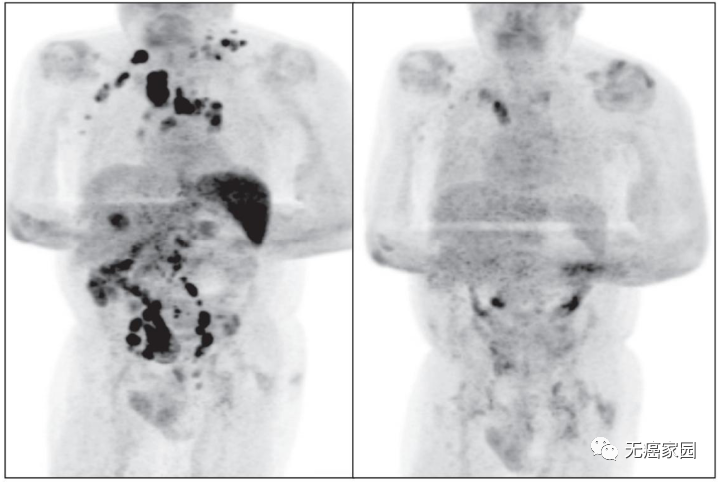

虽然期间有轻微的CAR-T疗法副作用,但神奇的是,短短的30天内,她的肿瘤完全消失。在附加的图像中显示了巨大的变化,左侧是取回CAR-T细胞前1周的扫描,右侧是1个月后的扫描。

2020年7月,阿达米进行了为期2年的CAR-T PET扫描,并完全缓解!现年61岁的她感觉自己挑战了人生的巨大困难,并打算对珠穆朗玛峰的攀登发起挑战!